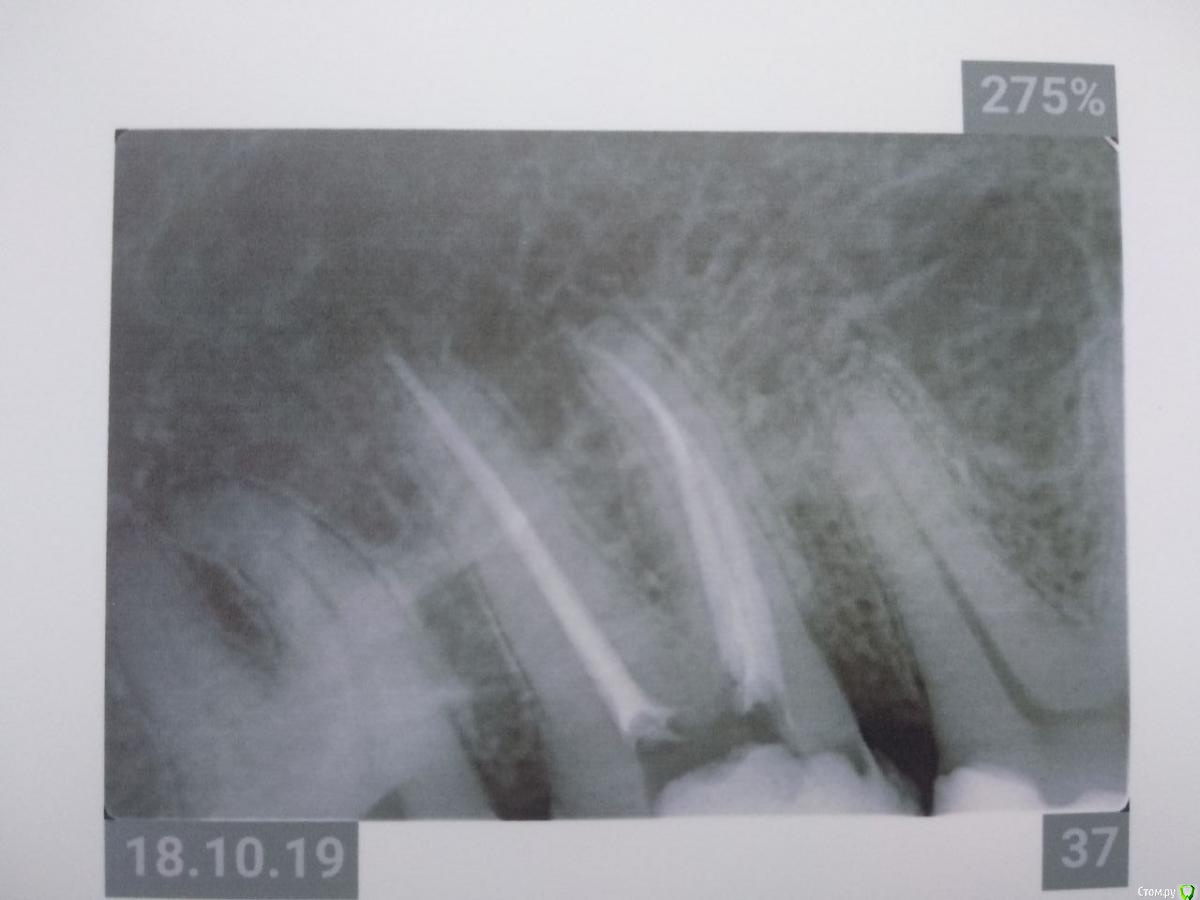

Здравствуйте! Откололся кусок зуба. 8 октября сделали КЛКТ (3Д снимок всех зубов). Вскрыли зуб, была проведена девитализация. Поставили диагноз: хронический фиброзный пульпит 37 зуба. 18 октября было проведено первичное лечение 3-х канального зуба эндомотором с использованием микроскопа и системы коффердам. Все каналы были запломбированы гуттаперчивыми штифтами на силлере методом латеральной конденсации Adseal, внутрь заложена ватка и поставлена временная пломба дентин-паста. 29 октября ортопед №1 посмотрел прицельный снимок (см. снимок зуба 2) и сам зуб, пломбу не снимал. Озвучил, что у меня низкая высота зуба, мне нужно установить культевую кобальт-хромовую вкладку и сверху покрыть металлокерамической коронкой зуб. Также сказал, что циркониевая вкладка мне не подходит из-за высоты. Однако, поскольку ортопед №1 уходил на обучение, мне было предложено обратиться в другую клинику к другому ортопеду. 1 ноября ортопед №2 посмотрев мой зуб без снимка заявил, что у меня сохранились три стенки у зуба и мне надо просто закрыть пломбой этой зуб. Поскольку ортопед №2 предложил диаметрально противоположное лечение зуба, то я решил обратиться в третью клинику. Ортопед №3 посмотрев снимок моего зуба, сам зуб, в том числе внутри (снял мою временную пломбу из дентина), заявил, что у меня низкая высота зуба и мне нельзя ставить культевую вкладку и коронку. И было предложено сделать вкладку из пресс керамики overlay. Также когда удалили временную пломбу у меня увидели кариес на этом зубе. В конце приема мне взамен снятой пломбы установили временную пломбу парасепт.

Покажите снимок до лечения, по вашему фото точно сказать есть ли кариес в этом зубе нельзя, возможно есть, рентгеновский снимок нижнего зуба, а вы выкладываете вверх корнями, поправте  это, и думаю стоит перелечить,  как минимум дистальный канал(корень), по вашему снимку определяется выведение гуттаперчи за пределы корня это не по стандарту, выведение силлера допускается. У форума нет задачи определять, кто и кого разводит на деньги! мы помогаем людям в их сложных клинических ситуациях. В случае приведения пломбировки корней к приемлемому виду, я бы закончил его лечение фиксацией пресскерамической вкладкой, покрывать депульпированные зубы жевательной группы пломбами крайне не желательно.

Спасибо за ответ. Перевернул снимок. Прицельного снимка до лечения не делали, только КЛКТ. Не знаю насколько подойдет снимок из КЛКТ, но прикрепил. Я правильно Вас понял, что мне пролечили плохо каналы под микроскопом, в частности дистальный канал, тк гуттаперча вышла за пределы корня? Мне нужно повторно перелечить этот канал под микроскопом?